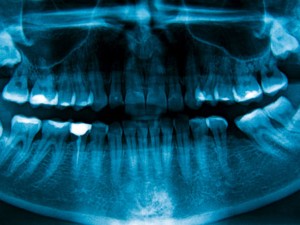

Odontologia: scanner lê e digitaliza imagens de raios X obtidas por

meio de placas constituídas por sais de terras raras, entre outros materiais

Voltado para aplicação em odontologia – por ser uma das áreas da saúde que mais demandam a utilização de raios X –, o equipamento possibilitará o desenvolvimento no Brasil dessa nova tecnologia, ainda dominada por poucos países, que está transformando o modo como a radiologia é feita no mundo, avaliam os pesquisadores participantes do projeto.

O scanner lê e digitaliza imagens de raios X obtidas por meio de placas constituídas por sais de terras raras, entre outros materiais. Ao incidir raios X sobre essas placas, as cargas eletrônicas das moléculas das substâncias que compõem o material são excitadas e entram em um estado energético chamado metaestável (diferente de seu estado de equilíbrio).

O scanner lê e encaminha quase em tempo real a imagem gerada pela placa para um monitor de alta resolução – semelhante aos utilizados em exames de ultrassonografia. Um software específico processa e gera a radiografia com altíssima resolução, que pode ser armazenada ou enviada pela internet.

“A radiologia digital permite fazer quase uma microscopia com raios X por meio de imagens com resolução praticamente em nível molecular”, disse Bagnato à Agência FAPESP. “Tudo depende de quão finamente conseguimos focalizar o laser de leitura.”

Os pesquisadores também desenvolvem softwares para processamento de radiografia digital com novos aplicativos a fim de possibilitar aos profissionais de saúde da área odontológica não somente visualizar a radiografia, mas obter informações como a densidade óssea e os danos encontrados em um determinado dente do paciente, por exemplo.